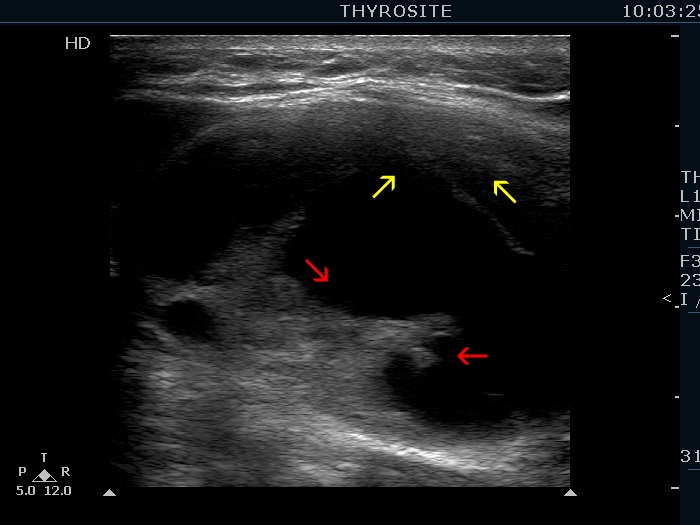

Elastography - case 2145 (ultrasonographic picture 3b)

Right lobe, longitudinal scan. Compare the solid part located in the ventral (yellow arrows) and in the dorsal (red arrows) surface of the nodule. The latter is more echogenic because of the enhancement of the echo signal caused by the cystic fluid.